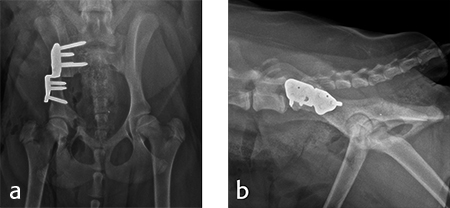

Angles of subluxation (10°) and reduction (30°) of the right hip were measured under anesthesia and the patient was placed in dorsal recumbency. A 7 mm portion of the right pubic body was excised. The patient was repositioned into lateral recumbency. A right ilial osteotomy was made immediately caudal to the sacrum. A 25° DPO/TPO plate was attached to the caudal ilial bone segment using locking 3.5 mm screws in the three stacked combi holes. The caudal acetabular segment was rotated laterally until the cranial aspect of the plate was in contact with the lateral aspect of the cranial ilial segment. The osteotomy site was compressed, and the plate was secured to the cranial ilial bone segment using a 3.5 mm cortical screw in the LCP combi hole in the cranial side of the plate. Three additional 3.5 mm locking screws were placed in the remaining stacked combi holes in the cranial segment of the plate.

Postoperative radiographs revealed reduction in subluxation with capture of the femoral head in the right coxofemoral joint (Fig 4). Palpation of the hip revealed good stability of the right hip. Activity was restricted to leash walk only for 6 weeks postoperatively. Radiographic examination 7 weeks following surgery revealed healing of the ilial osteotomy, stable implants, and excellent coxofemoral conformation and stability (Fig 5).